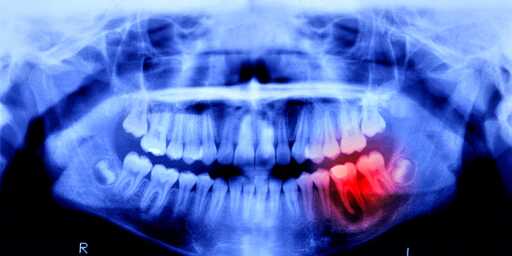

This development follows years of study around a particularly antibody named Uterine sensitization–associated gene-1 (USAG-1), which has been shown to inhibit the growth of teeth in ferrets and mice. Back in 2021, scientists from the Kyoto University—who will also be involved in future human trials—discovered a monoclonal antibody (a technique usually used in fighting cancer) that disrupted the interaction between USAG-1 and molecules known as bone morphogenetic protein, or BMP.

Now, scientists will see just how similar, because humans are undergoing a similar trial. Lasting 11 months, this study focuses on 30 males between the ages of 30 and 64—each missing at least one tooth. The drug will be administered intravenously to prove its effectiveness and safety, and luckily, no side effects have been reported in previous animal studies.

If all goes well, Kitano Hospital will administer the treatment to patients between the ages of 2 to 7 who are missing at least four teeth, with the end goal of having a tooth-regrowing medicine available by the year 2030. While these treatments are currently focused on patients with congenital tooth deficiency, Takahashi hopes the treatment will be available for anyone who’s lost a tooth.